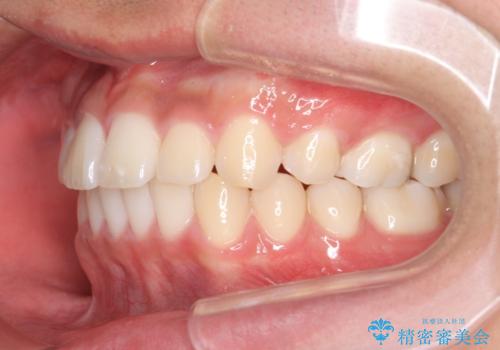

抜歯矯正の長期予後(術後8年目)

- ワイヤー矯正による治療後7年以上経過した患者様です。当時上の小臼歯を2本抜歯しています。

10代で矯正治療を行い、現在20代になられています。

矯正後8年目になりますが、並びも綺麗に保持でき、また上下の歯がさらにしっかり咬んできているのがわかります。

定期的にメンテナンスにきていただき、特に歯の健康状態にも問題がありません。

下は歯につけるタイプのワイヤーを貼っています。

上は取り外し式の装置を就寝時使っていただいています。